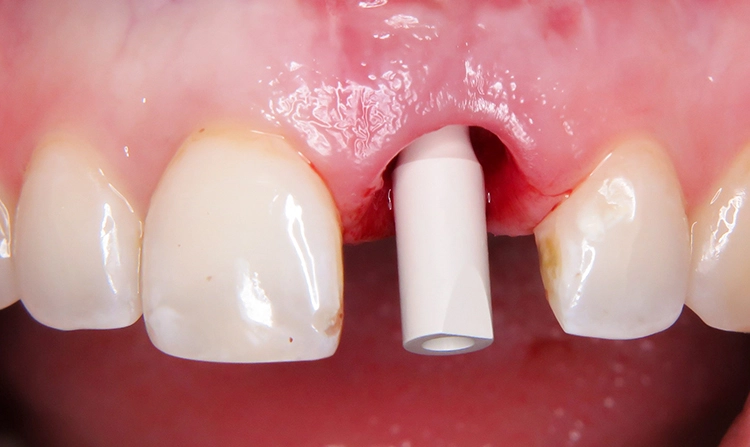

Chairside-Scanning: Digitaler Implantatscan statt analoger Abformung

Das Herstellen der Sofortversorgung in der Zahnarztpraxis erfolgte CAD/CAM-gestützt mit dem 3D-Drucksystem Straumann® CARES® P20. Hierfür wurde die Situation nach der Implantatinsertion auf direktem Weg – chairside – digitalisiert. Auf den Umweg einer konventionellen Abformung mit Modellherstellung und der anschließenden Rückführung in einen digitalen Datensatz (Laborscanner) kann auf diese Weise verzichtet werden. Auf das inserierte Implantat regio 21 wurde der Scanbody aufgebracht (Abb. 9 und 10). Mit dem Intraoralscanner (Trios, 3Shape) konnte nun die Implantatposition erfasst und in der Software abgespeichert werden (Abb. 11 und 12).